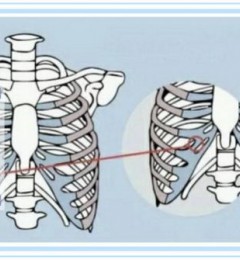

双鄂=上颚(上颌骨)+下颚(下颌骨)

(图中带颜色部位)

▲图片来自《3Dbody》

▲双鄂手术方式示意图